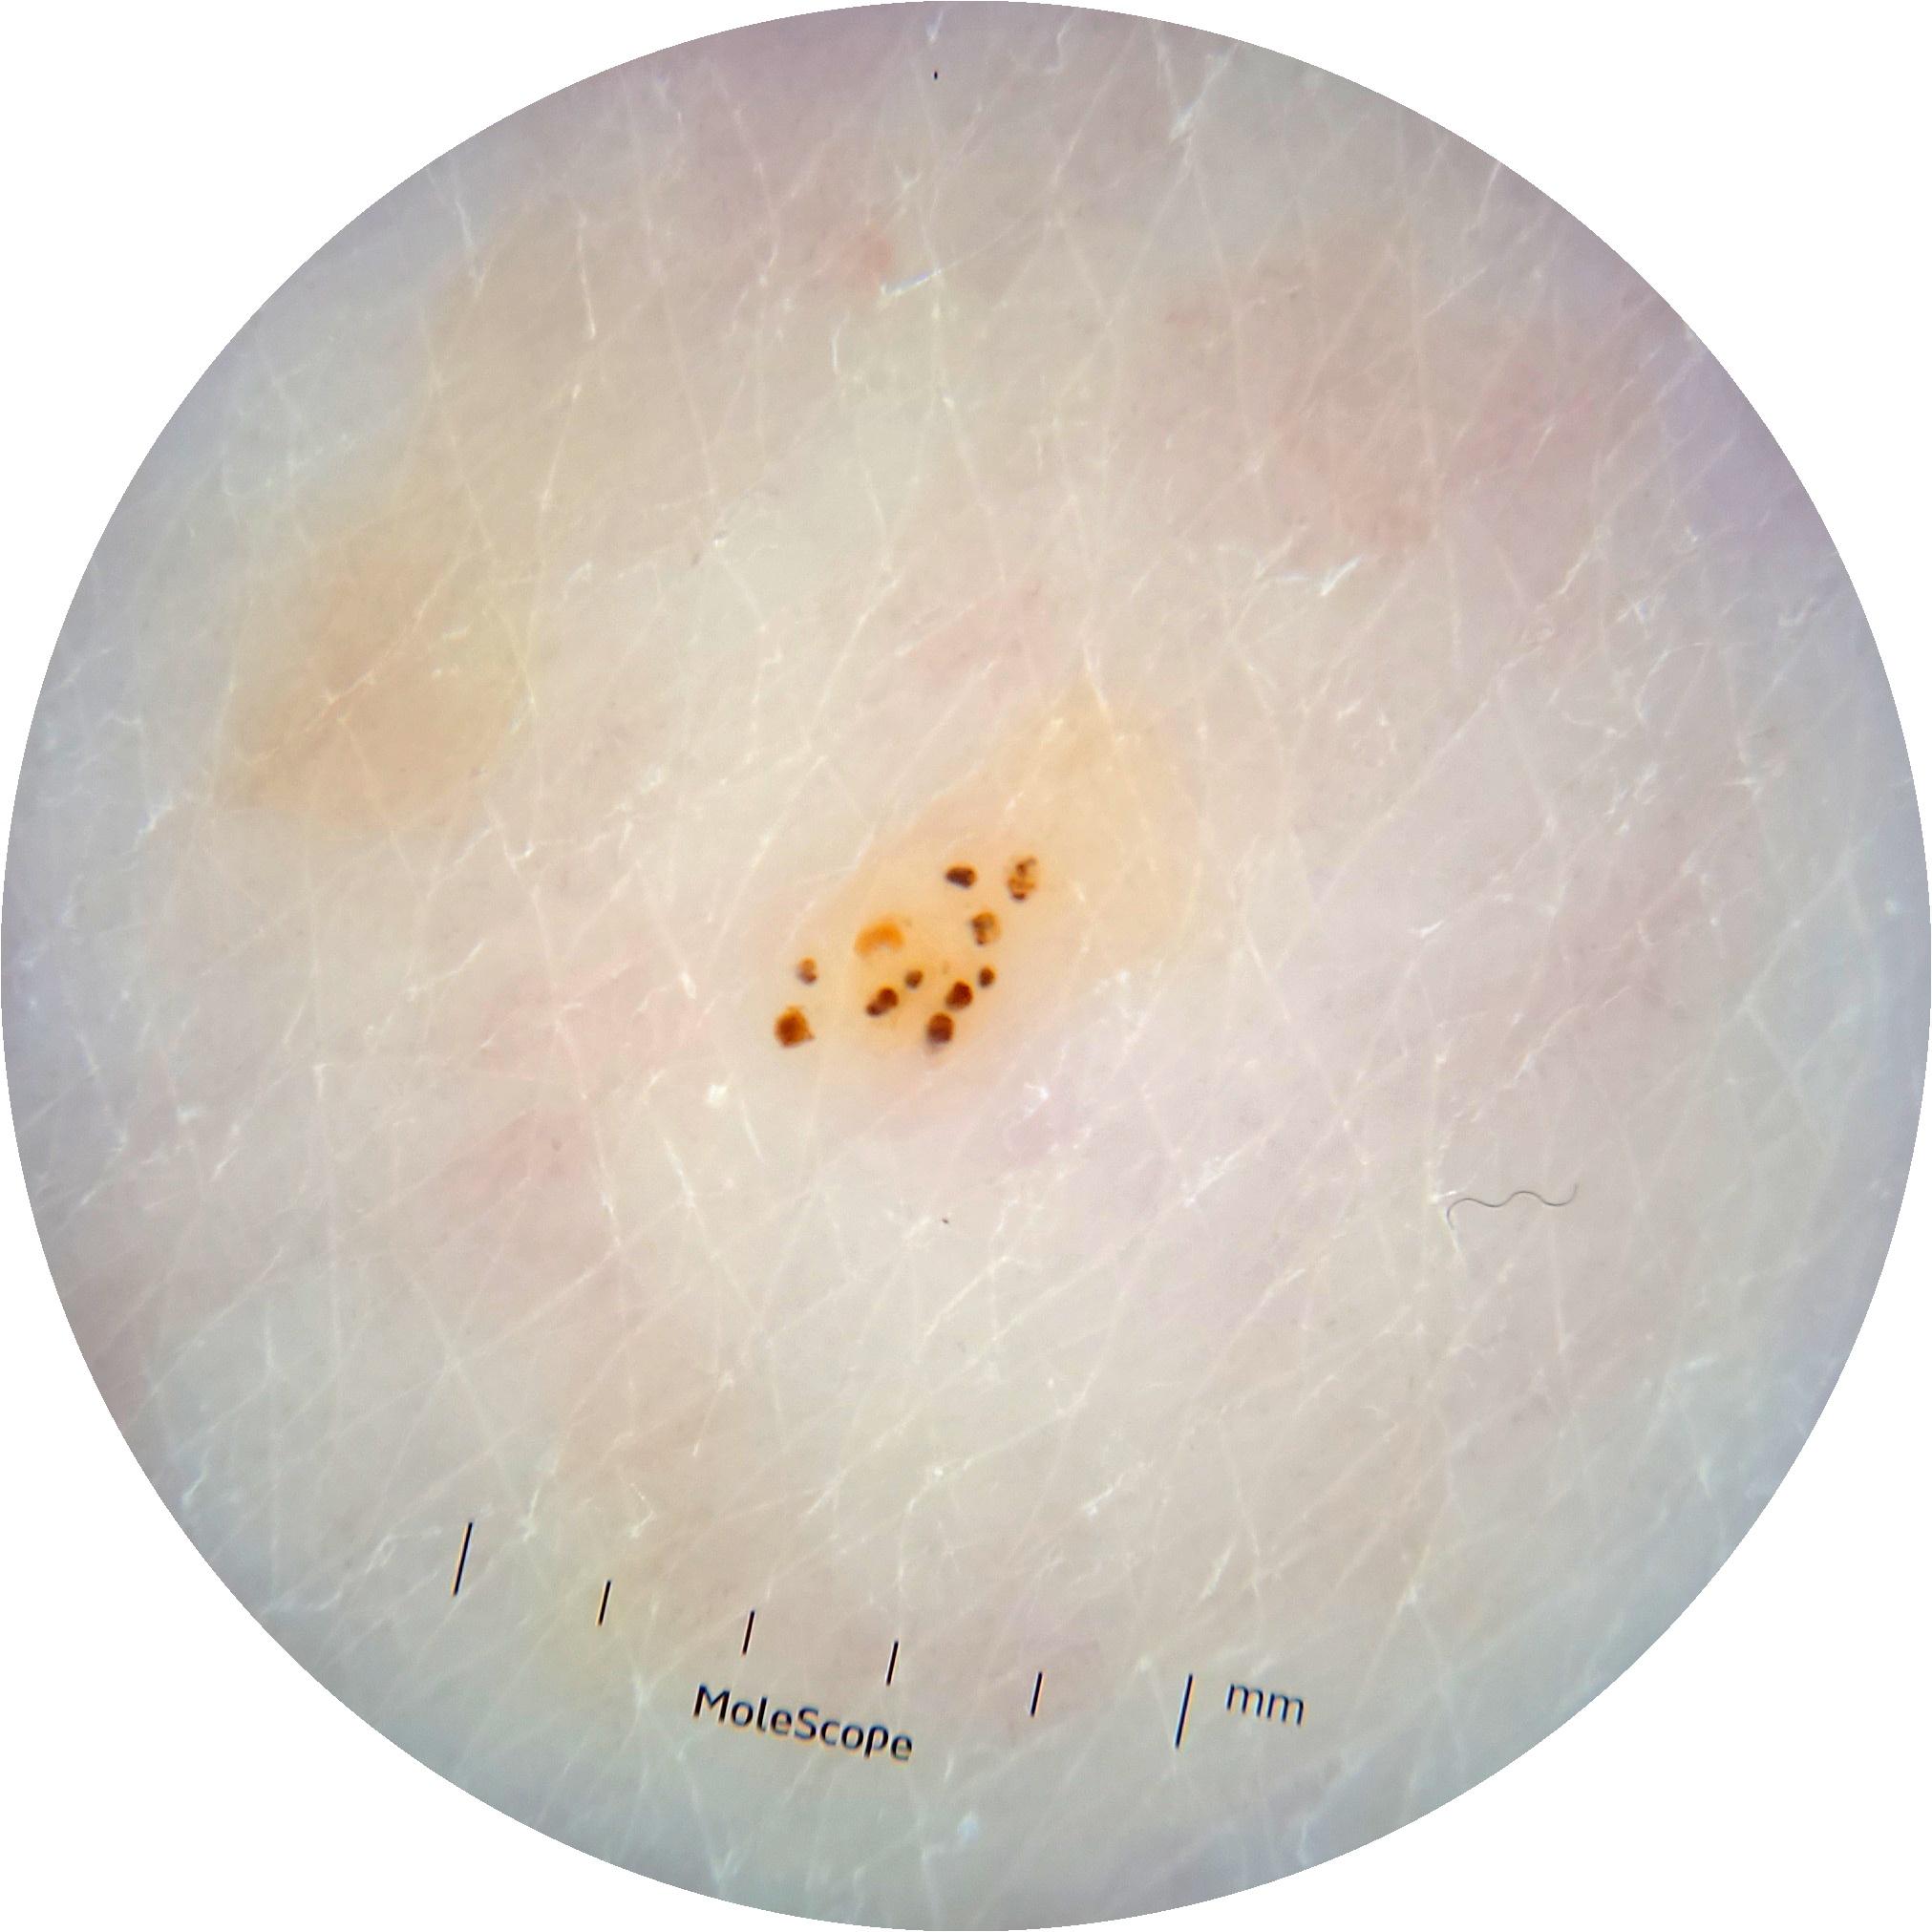

ISIC_6363669

923 x 923

acquisition_day 264

age_approx 65

anatom_site_1 Trunk

anatom_site_2 Anterior trunk

anatom_site_general anterior torso

diagnosis_1 Benign

diagnosis_confirm_type single image expert consensus

image_type dermoscopic